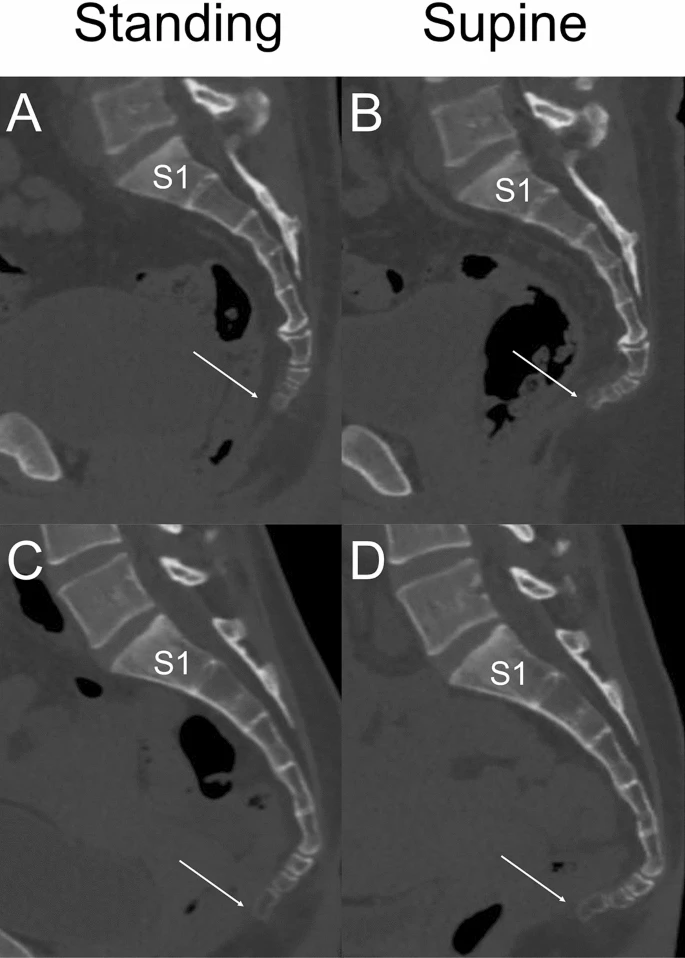

体位による変化:座位で体重がかかると尾骨は前屈し、立位では仙骨との角度が変化します。CT研究では、立位と仰臥位で仙尾骨角に有意な差があることが報告されています。

こちらの画像では仙尾関節の動きよりも尾椎間での運動量が大きいですね。

連動性:腰椎前弯や仙骨のニューテーション(前傾)に伴って、仙尾関節は屈曲方向に動きます。逆に仙骨カウンターニューテーションでは尾骨は伸展方向に動きます。このことから、腰椎や骨盤の位置関係で仙尾関節の状況は変わるので、全体の関連性から尾骨を見ていくことが大切だと感じました。組織の質感や可動範囲を確認しながら、アプローチの優先度を判断していく必要ありそうですね。